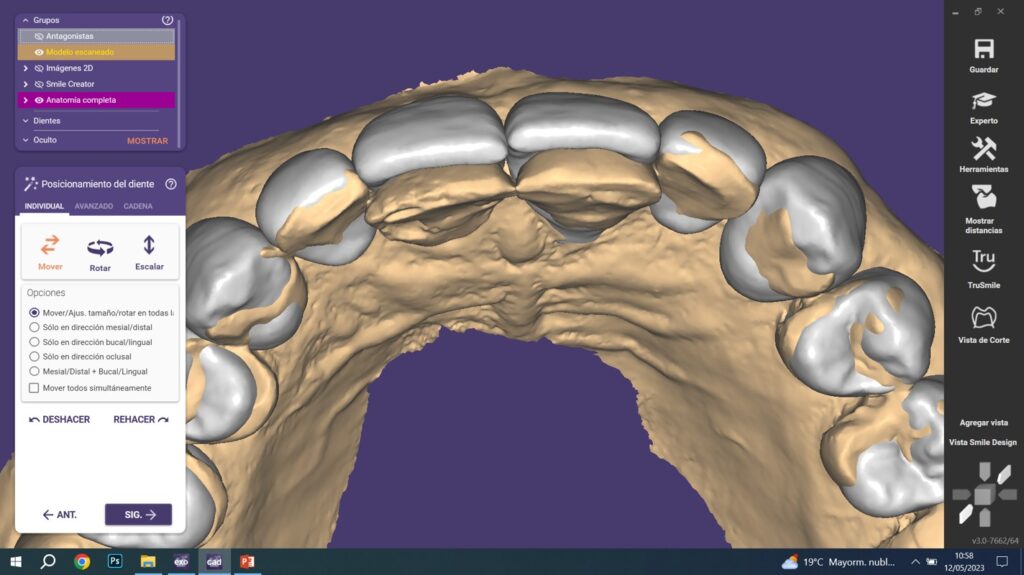

Simulación estética: visualizando el resultado final

Antes de proceder con el tallado y la colocación de las carillas, realizamos una simulación estética. Esta etapa es crucial para:

- Ajustar la forma y el tamaño de los dientes de acuerdo con la proporción facial de la paciente.

- Asegurarnos de que el resultado final sea acorde a las expectativas tanto funcionales como estéticas.

La paciente pudo visualizar el resultado final antes de realizar cualquier intervención irreversible, lo que aportó seguridad y confianza en el proceso.